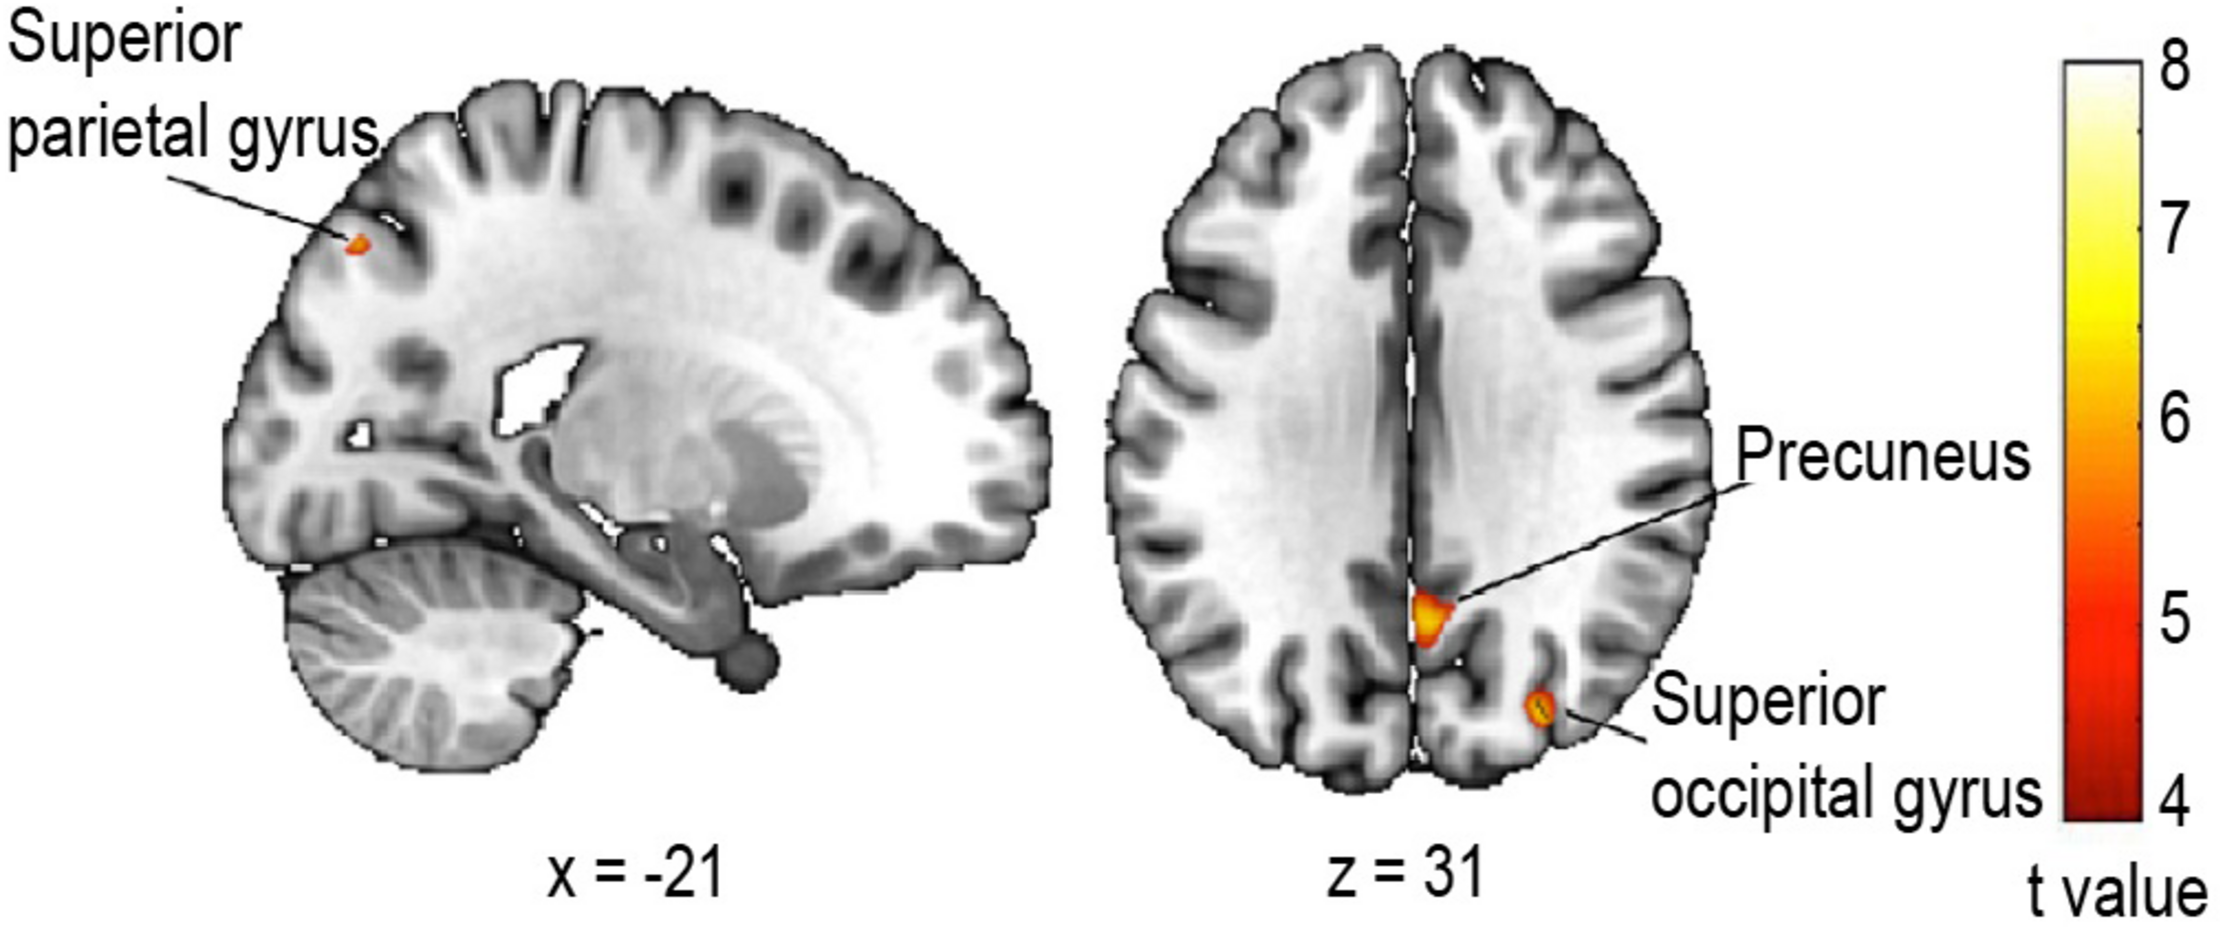

Association Between Change in Walking Speed and Cortical Atrophy

Finally, we tested whether the change in walking speed on the first trial compared to the last was associated with gray matter atrophy in older adults, by performing a voxel-based morphometry study. The multiple regression analysis revealed a significantly decreased gray matter volume in parietal and occipital regions (Figure 5) related to an increased change in walking speed. More specifically, we observed a reduced gray matter volume of the left superior parietal lobule [BA 7, t(14) = 7.70, pcorrected_FWE = 0.038, r = 0.90, k = 10], the superior aspect of the occipital lobe on the lateral surface of the right hemisphere [BA 39, t(14) = 7.47, pcorrected_FWE = 0.030, r = 0.89, k = 28] as well as of the right precuneus [BA 31, t(14) = 7.31, pcorrected_FWE = 0.022, r = 0.89, k = 52].

Figure 5. Regression analysis between gray matter volume and change in walking speed. Areas where the negative correlation proved significant: Superior parietal lobule, left hemisphere, t = 7.70; peak coordinate x = –20, y = –76, z = 45 (k = 10); Precuneus, right hemisphere, t = 7.41 peak coordinate x = 4, y = –60, z = 30 (k = 52); Superior aspect of occipital lobe on the lateral surface, right hemisphere, t = 7.47 peak coordinate x = 30, y = –81, z = 32 (k = 28). Statistical threshold p < 0.05 FWE (Family Wise Error) corrected for multiple comparisons, extended threshold fixed at k = 10 voxels.

Given the neuroimaging evidence of greater cognitive involvement in walking with older age (Zwergal et al., 2012; Hamacher et al., 2015) and the differential recruitment of brain areas under CMI (Leone et al., 2017), we explored possible neuroanatomical correlates of our hypothesized CMI during spatial learning. More specifically, the evidence of regional atrophy being linked to slowing of gait and the fact that gray matter volume accounts for functional changes in cerebral activity in older age (Kalpouzos et al., 2012) led us to examine whether we could find associations between age-related changes in brain structures and walking speed in an ecological context. The regression analysis on grey matter (GM) volume in a subset of our population revealed interesting and pertinent results. The change in walking speed between the first and last trials was negatively correlated with GM volume in parts of the superior parietal lobule, superior aspect of the occipital lobe on the lateral surface and precuneus. These loci are neighboring association areas lying near the border of the occipital and parietal lobes and they are indeed part of the network involved in locomotor control (Wang et al., 2008), including visually-guided walking (Malouin et al., 2003) and they are associated with walking speed (Callisaya et al., 2014; Blumen et al., 2019). Importantly, these areas are involved in processes that are crucial for spatial navigation. Posterior parietal areas, including the superior parietal lobule and precuneus, play an essential role in visuo-spatial imagery and attention, episodic memory, self-processing and internal representations of the self and the environment (Corbetta et al., 1995; Wolpert et al., 1998; Suchan et al., 2002; Cavanna and Trimble, 2006). Further, recruitment of the precuneus was shown during explicit learning in young, but not older adults (Dennis and Cabeza, 2011). Along with the superior aspect of the occipital lobe (collectively referred to as the superior parieto-occipital cortex), these areas also participate in the encoding or retrieval/imagery of space during navigation tasks, in both egocentric and allocentric reference frames, thus contributing to spatial learning (Committeri et al., 2004; Frings et al., 2006; Gramann et al., 2010; Weniger et al., 2010; Barra et al., 2012).